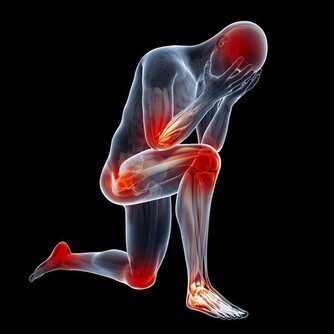

常常覺得手麻或是腳麻嗎?小心這些小症狀都是你的身體在跟你求救!!千萬不能忽視它啊...!!!

心臟有問題時————左邊手臂會酸、麻、痛。

肝臟有問題時————小腿晚上睡覺時容易抽筋。